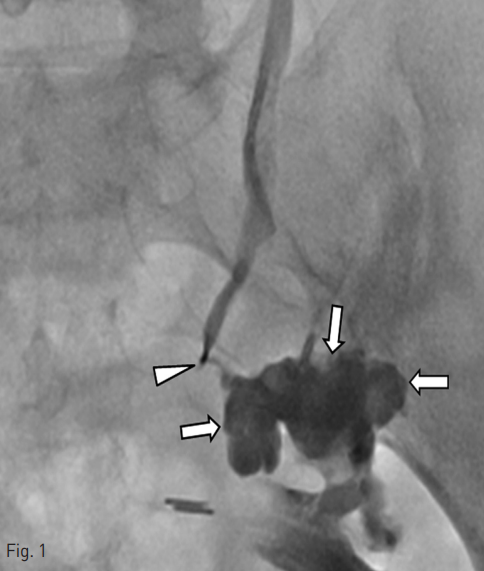

경피적 신루 도관 (percutaneous nephrostomy tube)을 통해 시행한 우측 순방향 요관조영술에서 우측 요관의 원위부에서의 조영제 누출이 확인되었다 (Fig. 1).

Fig. 1

Right antegrade ureterogram through the PCN tube shows contrast medium leakage (arrows) from the distal tip (arrowhead) of the right ureter.